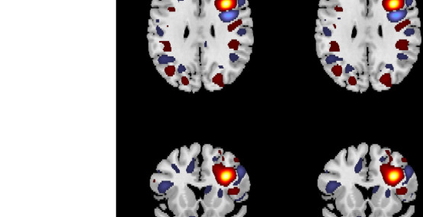

In the last two decades, unsupervised latent variable models---blind source separation (BSS) especially---have enjoyed a strong reputation for the interpretable features they produce. Seldom do these models combine the rich diversity of information available in multiple datasets. Multidatasets, on the other hand, yield joint solutions otherwise unavailable in isolation, with a potential for pivotal insights into complex systems. To take advantage of the complex multidimensional subspace structures that capture underlying modes of shared and unique variability across and within datasets, we present a direct, principled approach to multidataset combination. We design a new method called multidataset independent subspace analysis (MISA) that leverages joint information from multiple heterogeneous datasets in a flexible and synergistic fashion. Methodological innovations exploiting the Kotz distribution for subspace modeling in conjunction with a novel combinatorial optimization for evasion of local minima enable MISA to produce a robust generalization of independent component analysis (ICA), independent vector analysis (IVA), and independent subspace analysis (ISA) in a single unified model. We highlight the utility of MISA for multimodal information fusion, including sample-poor regimes and low signal-to-noise ratio scenarios, promoting novel applications in both unimodal and multimodal brain imaging data.